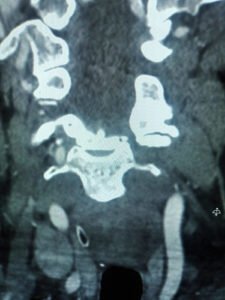

Despite these efforts, a subsequent CT angiogram revealed extensive basilar and vertebral thrombosis, leading to consideration for thrombectomy.

Unfortunately, the patient’s condition worsened, and thrombectomy wasn’t feasible due to the territory of the infarcts. The patient was made comfortable and passed away shortly thereafter.